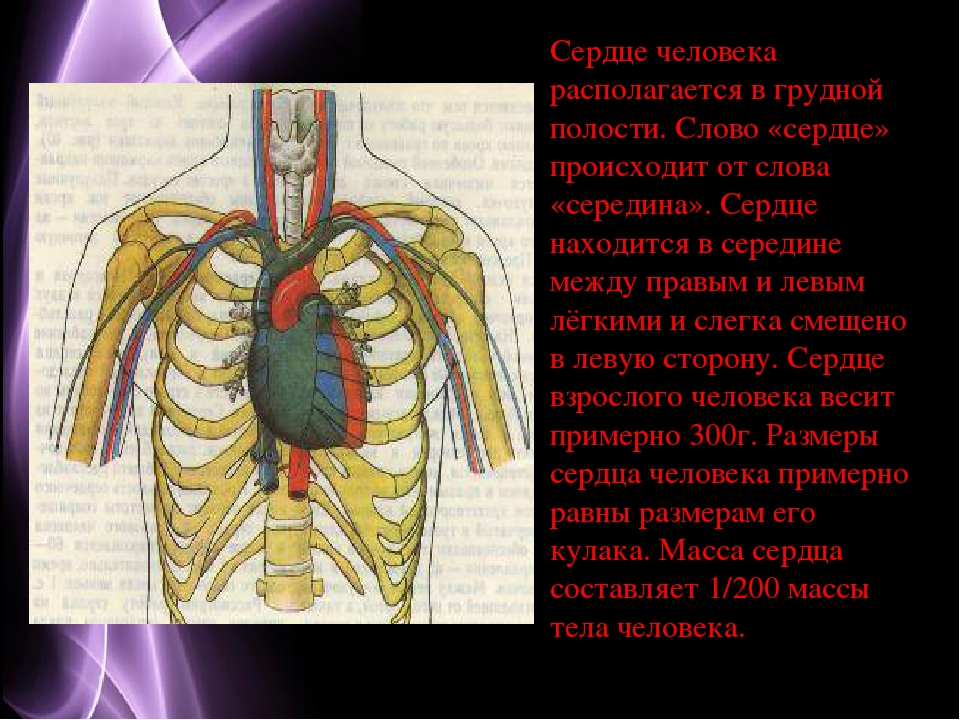

Где находится сердце у человека.

Сердце у человека располагается.

Сердце у человека располагается в грудной полости.

Расположение сердца у человека.

Анатомическое расположение сердца.

Сердце в грудной клетке расположено.

Где расположено сердце у человека анатомия.